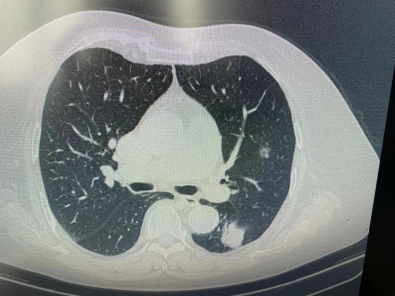

原来何奶奶的肺结节一个位于左下肺,直径约3.0cm,考虑为中期肺癌;另一个位于左上肺较深的位置,直径约1.2cm,考虑为早期肺癌,需及时手术治疗。

第二步,陈前顺副主任进行CT引导左上肺肿瘤热消融,整个过程仅耗时10分钟。